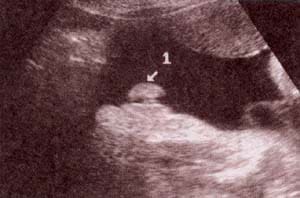

Diagnóstico Prenatal -  bolsa escrotal y su contenido Diagnóstico Prenatal -  30 semanas. se observan los testículos

fig. 51.– (a). bolsa escrotal y su contenido. 25 semanas. fig. 51.– (b). 30 semanas. se observan los testículos en un corte perpendicular al polo pélvico.